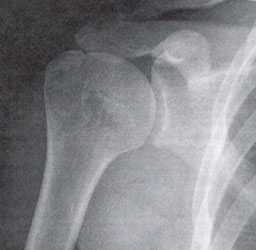

Наиболее информативными являются инструментальные методы исследования. Рентгенография используется редко, поскольку этот метод позволяет оценить лишь состояние костной ткани, а о повреждении связочного аппарата с ее помощью можно судить косвенно. КТ и МРТ позволяют комплексно оценить состояние плечелопаточного сочленения, определить состояние мягких тканей, расстояние между костными структурами. Эти методы позволяют не только выявить болезнь, но и определить оптимальную тактику лечения.

Импинджмент-синдром.а. МРТ плечевого сустава, б. рентгенография плечевого сустава.